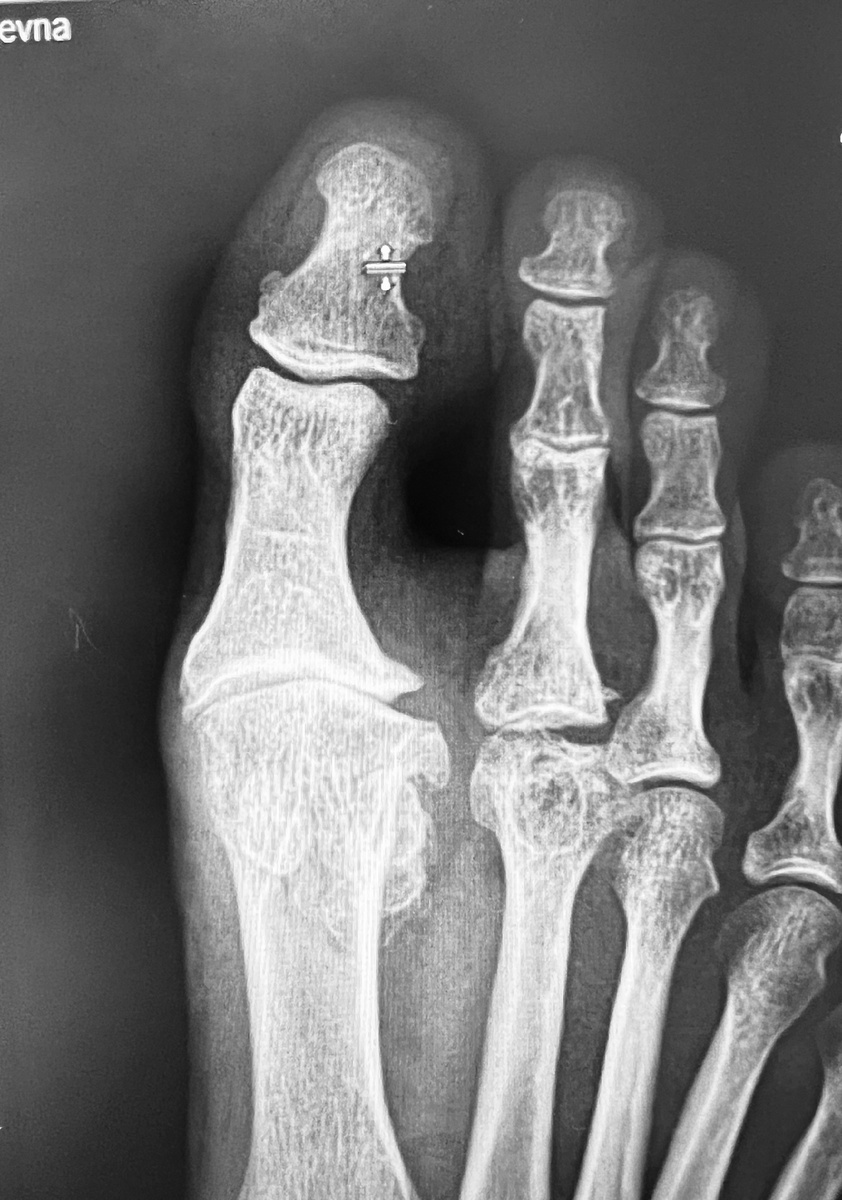

Если показать вот эту рентгенограмму рентгенологу, он с удовольствием опишет признаки артроза первого плюснефалангового сустава, разрушение головки второй плюсневой кости, дополнительную тень в области наружной сесамовидной кости. Может быть, даже угол между первой и второй плюсневыми костями посчитает. Но - голову даю на отсечение - в описании рентгенограммы не будет ни слова об избыточной длине первой плюсневой кости. А она очевидна. Дальше покажу, где это.

А вот так это выглядит на рентгене. Нижняя желтая черта показывает длину первой плюсневой кости. Вся кость над чертой (слева) - лишняя (в смысле длины). Справа та же кость уже укорочена до нормы. Верхняя желтая черта показывает одновременно уменьшившуюся длину большого пальца. Даже несмотря на исправление и формы пальца, и длины первого луча.